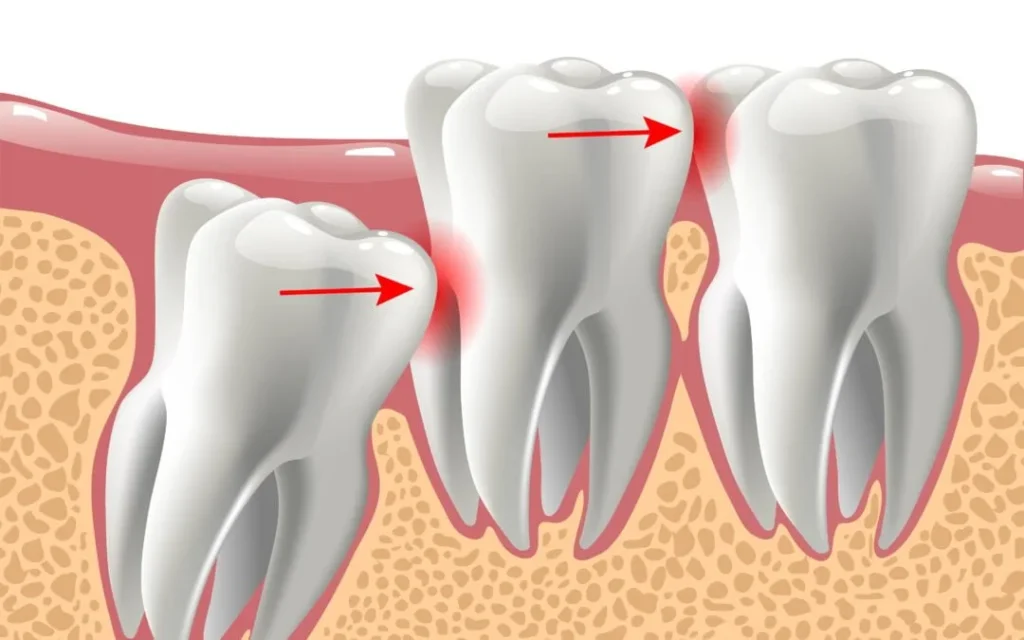

Wisdom teeth often erupt incorrectly, causing pain, swelling, infection, or pushing other teeth out of alignment. At Nanda Dental & Medical Speciality Centre, we specialize in painless and minimally invasive wisdom tooth removal using advanced techniques and digital diagnostics — ensuring fast relief and comfortable recovery.

Impacted Tooth

Tooth stuck inside the bone or gums causing continuous pressure and pain.

Crowding & Shifted Teeth

Wisdom teeth push adjacent teeth, causing crowding or crooked alignment.